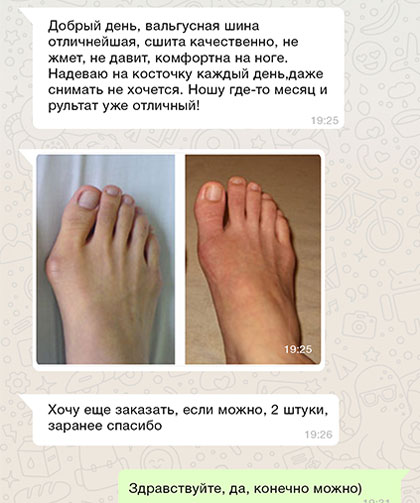

До использования

После 1,5 месяца использования шины FootRelax